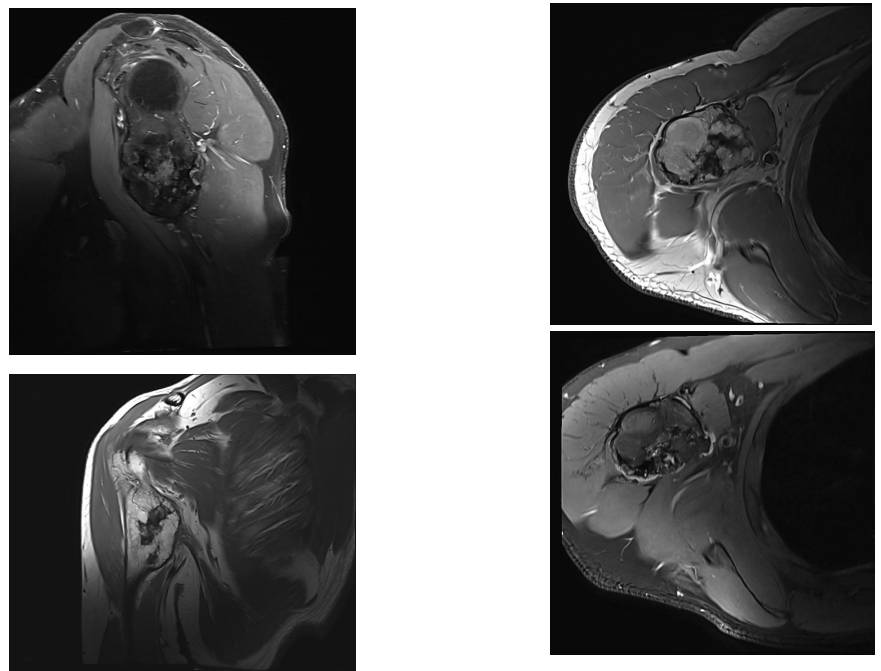

Ameliyat Öncesi: MR’da kitlenin vasküler yapılara yakınlığı görülmekte